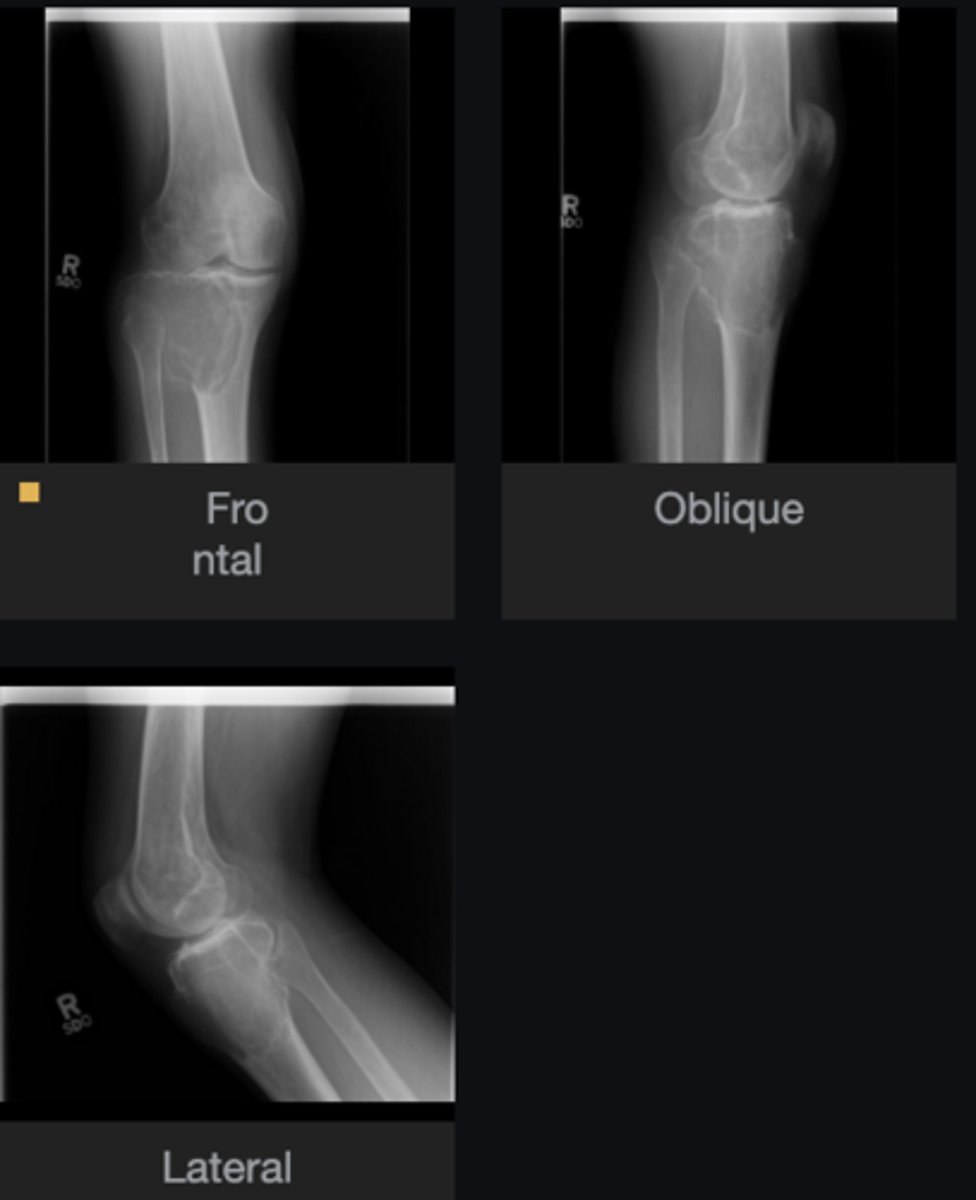

- Anterolateral distal tibia

- Metaphysis

- Septation

- Cortical thinning

- Geographic

- Sclerotic border

- Fibrous matrix

Describe the lesion

<p>Describe the lesion</p>

Non-Ossifying Fibroma

Diagnosis?

<p>Diagnosis?</p>

- Look for fracture

- Refer to orthopedist

Next step?

<p>Next step?</p>